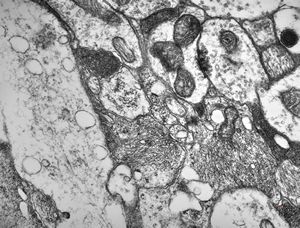

rabbit spinal cord trauma